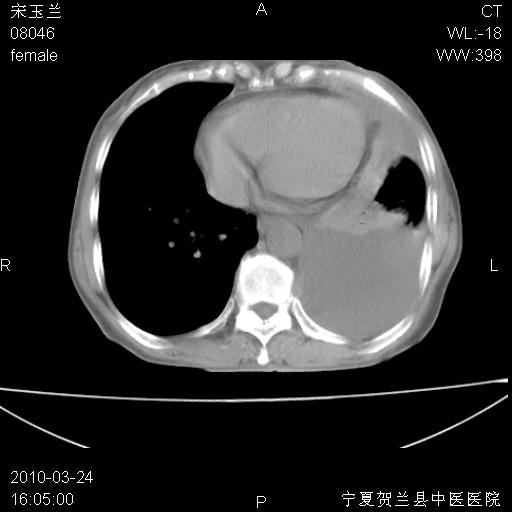

以下是引用zxl51642在2010-3-24 18:49:00的发言:[br]结合乳腺癌术后病史,考虑双肺及纵隔淋巴结多发转移、左侧胸膜转移并左侧大量胸水、左下肺膨胀不全。